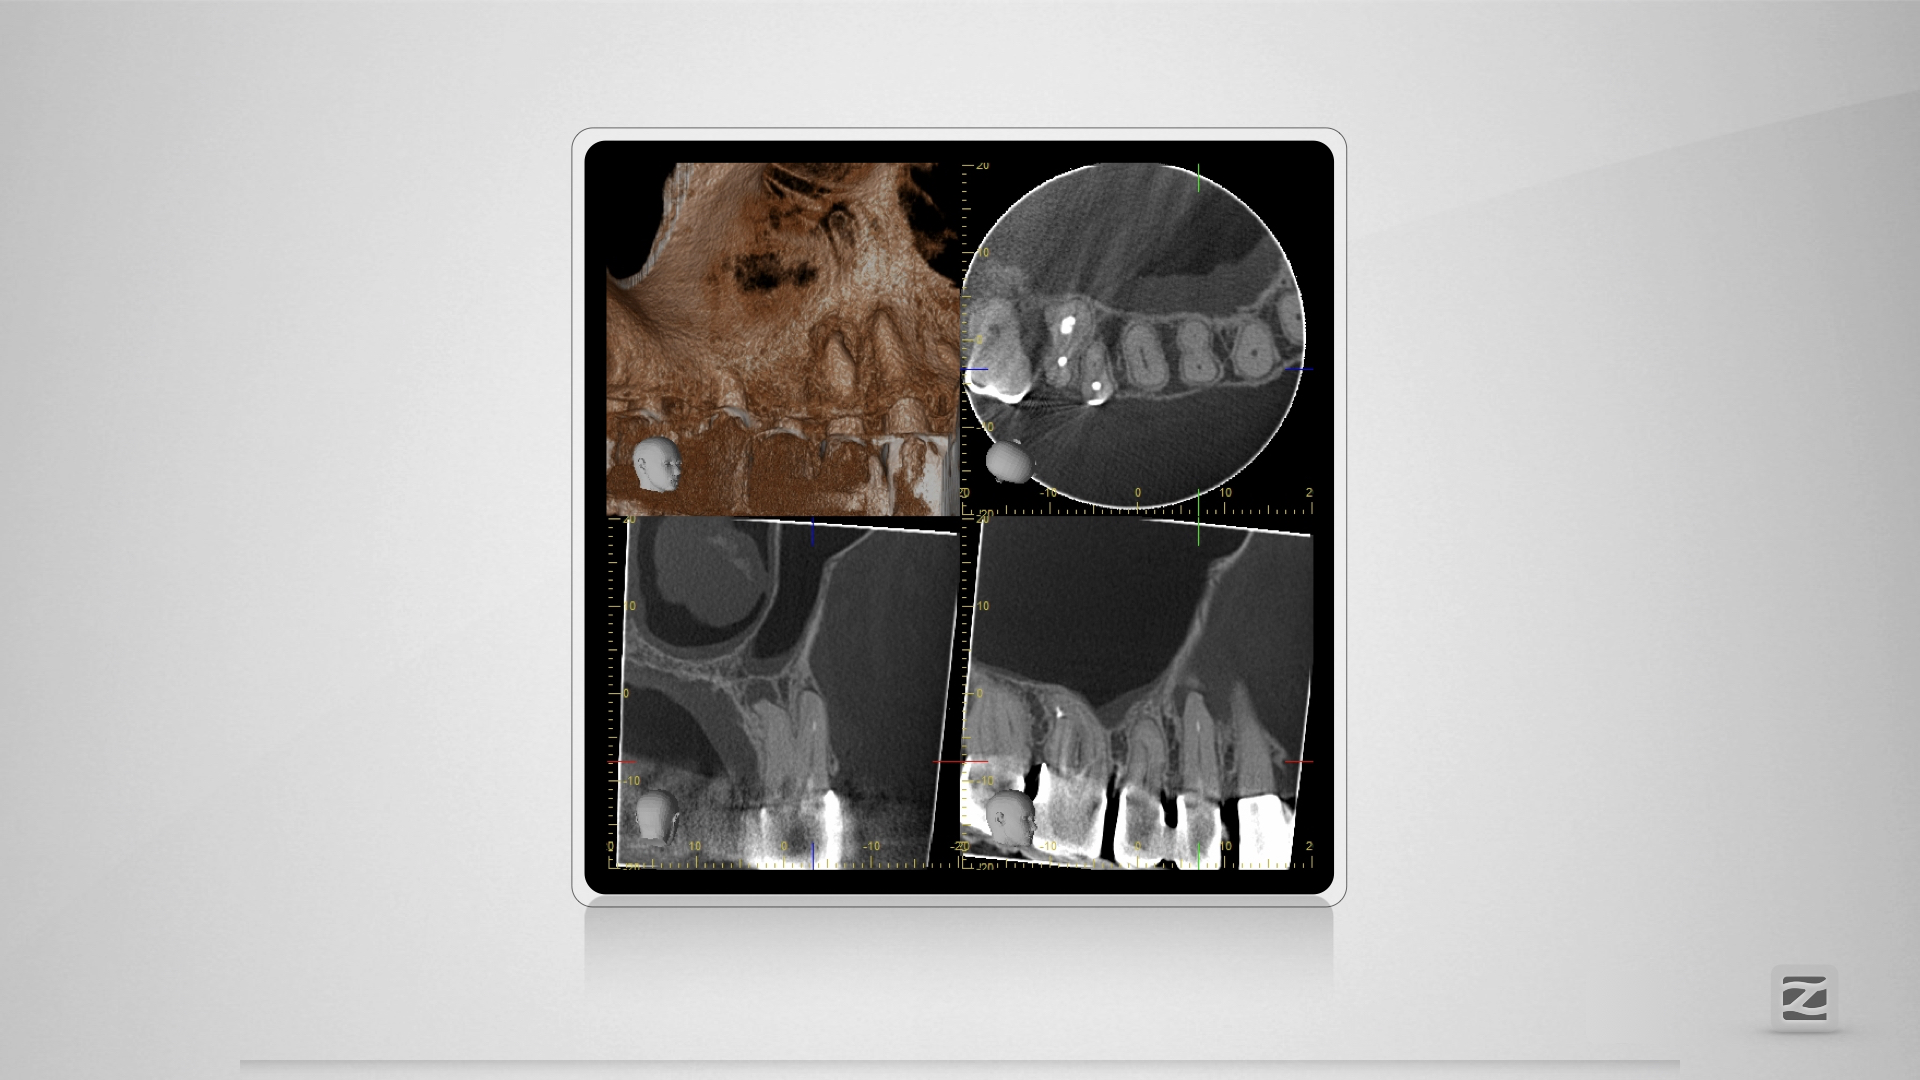

14D.005

Dummheit gehört bestraft.